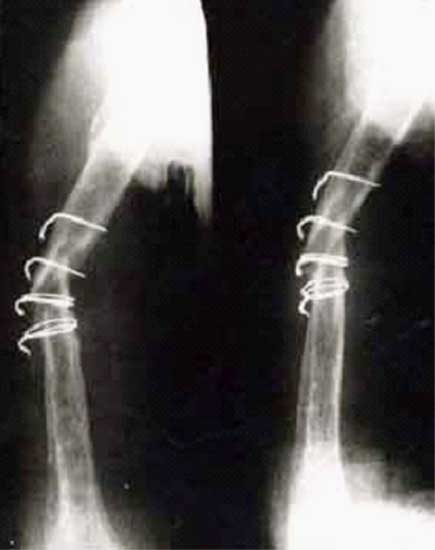

胫骨多段骨折外固定架术后1年,形成骨不连。取除外固定架,

改用髓内钉固定,6个月后骨折愈合。